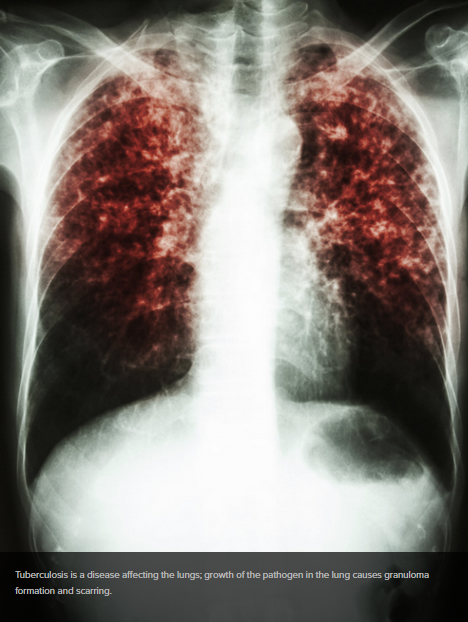

Tuberculosis continues to be the most serious cause of death from a single infectious micro-organism. Drug resistant tuberculosis is a particularly insidious manifestation of this disease for which alternative approaches to conventional therapy are required to facilitate treatment. Despite heroic efforts to develop new drugs to treat tuberculosis a very small number are currently in late stage development. New strategies that involve consideration of the pharmaceutical properties of old and new drugs are needed to improve efficacy and facilitate approval of next generation combination therapies. Poor solubility and bio-availability of efficacious compounds commonly leads to discontinuation of their development. However, formulation approaches can be employed to improve these properties and alternative routes of administration may further increase their therapeutic effect.

We are collaborating on developing a new therapy for TB. By delivering the drug straight to the site where the organism mostly grows in a convenient and low cost inhaler we intend to produce a therapeutic strategy that lowers the amount of drug needed, can be delivered by users at home, and that may be effective against various forms of tuberculosis including drug resistant forms.